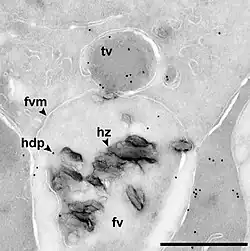

El parásito de la malaria desintoxica la hematina por medio de la biocristalización, convirtiéndola en cristales de β-hematina insolubles y químicamente inertes (la llamada hemozoína).[13][14][15] En Plasmodium, la vacuola alimenticia se llena con cristales de hemozoína, que tienen aproximadamente 100-200 nanómetros de largo y cada uno contiene aproximadamente 80 000 moléculas de hemo.[4] Cabe recalcar que la desintoxicación a través de la biocristalización es distinta del proceso de desintoxicación en los mamíferos, donde la enzima hemo oxigenasa cataliza la conversión del grupo hemo en biliverdina, Fe2+ y monóxido de carbono.[16]

Otros autores han descrito una proteína a la que llamaron Proteína de Desintoxicación de Hemo (Heme Detoxification Protein, HDP) y afirman que su acción es más potente que las de los lípidos o las proteínas ricas en histidina.[12] Múltiples mecanismos contribuyen a la formación de hemozoína.[21]